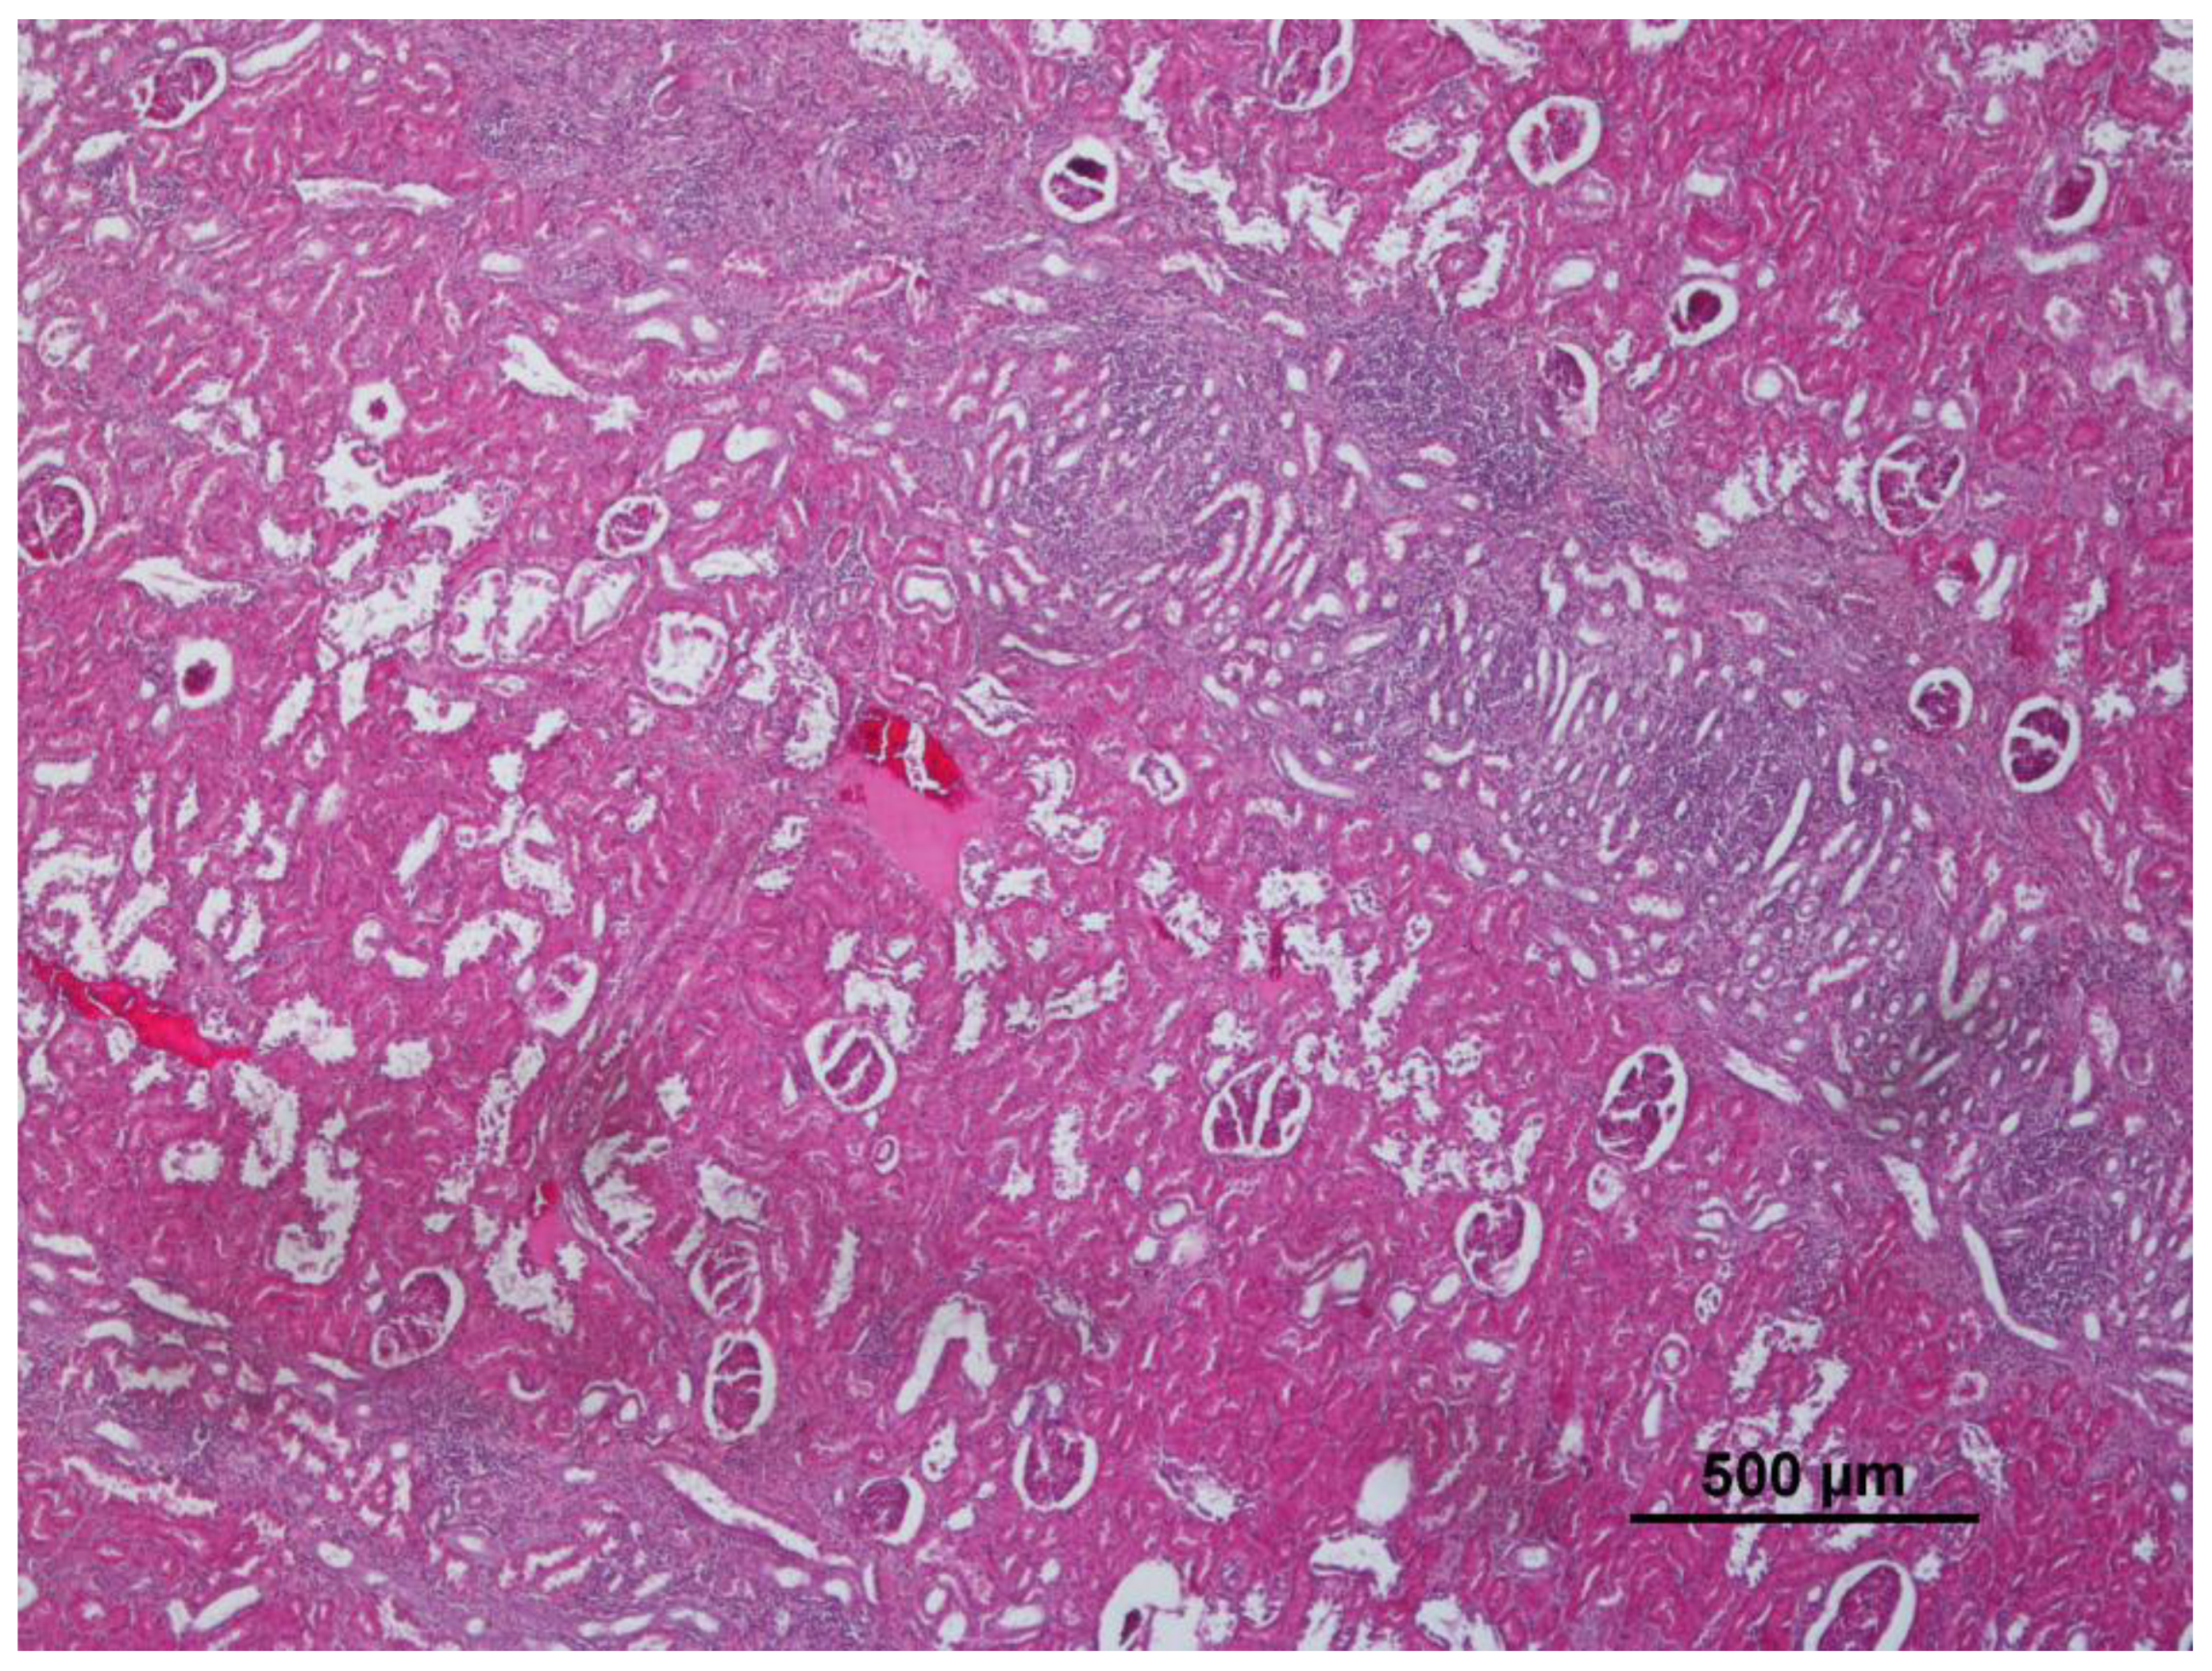

3.2. Liver

| Lymphoid hyperplasia | 26 | 36.1 | Cellular changes: cell swelling; hydropic change; vacuolar change | 24 | 33.3 | Non-purulent nephritis | 16 | 22.2 |

| Congestion | 6 | 8.3 | Congestion | 12 | 16.7 | Basal membrane thickening | 2 | 2.8 |

| Emphysema | 4 | 5.6 | Increase of eosinophils | 11 | 15.3 | Hypercellular glomeruli | 2 | 2.8 |

| Alveolar proteinosis | 1 | 1.4 | Increase of other white cells | 5 | 6.9 | Cellular infiltration | 2 | 2.8 |

| Silicates | 1 | 1.4 | Hemosiderin | 4 | 5.6 | Hemosiderin | 2 | 2.8 |

| Hemosiderin | 1 | 1.4 | Granulomatous hepatitis | 1 | 1.4 | Purulent nephritis | 1 | 1.4 |

| Subacute hepatitis | 1 | 1.4 | ||||||

| Steatosis | 1 | 1.4 | ||||||